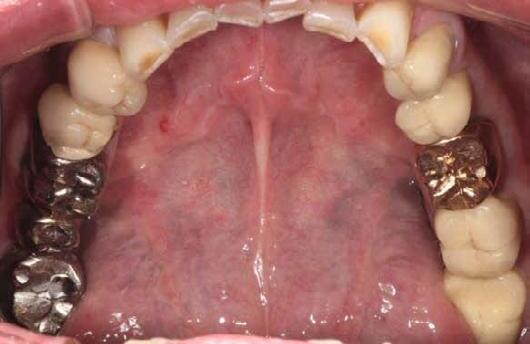

Why deep margin elevation?

Deep margin elevation will make the impression easier by moving the proximal margin of the restoration supra-gingivally, which is especially important for intra-oral scanning. It helps in avoiding periodontal surgical procedures. It makes isolation of the prepared tooth and luting of the final restoration easier.

Why immediate dentine sealing?

Resin infiltration into the dentine surface is more effective on freshly cut dentine because it is uncontaminated and clean. Immedciate Dentine Sealing protects dentine against contamination with bacteria or remnants of temporary cements. It prevents post-operative sensitivity by sealing dentine tubules. It increases bond strength of the final indirect restoration to the tooth. It often eliminates the need for anaesthesia during the cementation procedure (when the restoration is delivered in the next appointment).

Tips and Tricks

• Placing a rubber dam and isolating neighbouring teeth with teflon tape are always recommended.

• Use maximum air pressure to dry 1-PRIMER of G2-Bond to remove the solvent & residues of water.

• 1-PRIMER should be kept out of light as it contains photoinitiators.

• When doing immediate dentine sealing with G-Premio BOND, it is recommended to add a thin layer of G-aenial® Universal Injectable or a flowable composite on top.

1. Clean the tooth surfaces, rinse thoroughly and dry Apply G-Premio BOND Apply 1-PRIMER of G2-BOND Universal

5. Air dry to make a uniform bonding layer

4. Light cure

5. Fill in the undercuts with everX Flow®. Perform deep margin elevation if needed.

6. Remove unpolymerized layer. Expose enamel covered with adhesive with a fine grit diamond bur.

2A. G-Premio BOND

2B. G2-BOND Universal